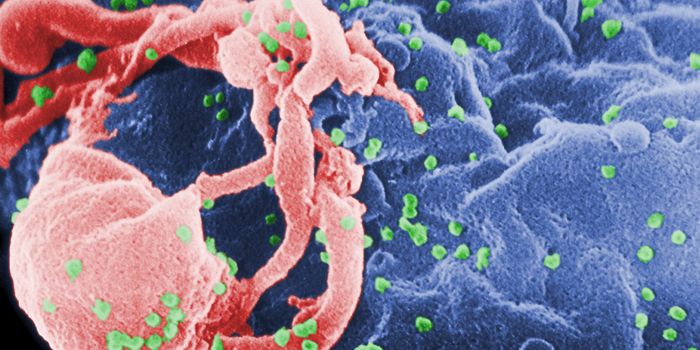

DEC 15, 2018Cell & Molecular BiologyResearchers have been trying to create a vaccine for HIV, the virus that causes AIDS, for decades.